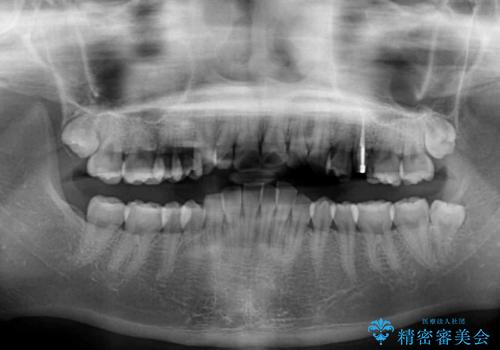

- デコボコの歯列が気になるとことで来院された患者様です。

歯列不正としては軽度であったため、インビザラインでもワイヤー装置でも対応可能でしたが、ご本人の希望によりインビザラインによる矯正治療を行うこととしました。

マウスピース矯正は、自己管理が非常に重要と事前にお伝えしておりましたが、毎日のマウスピース装着が遵守できず、ワイヤー装置での矯正治療へ変更することとなりました。

インビザラインからワイヤー装置へ変更すると、費用が追加となるため、ワイヤー装置は目立つものの費用を抑えることのできるメタルブラケットを使用しました。